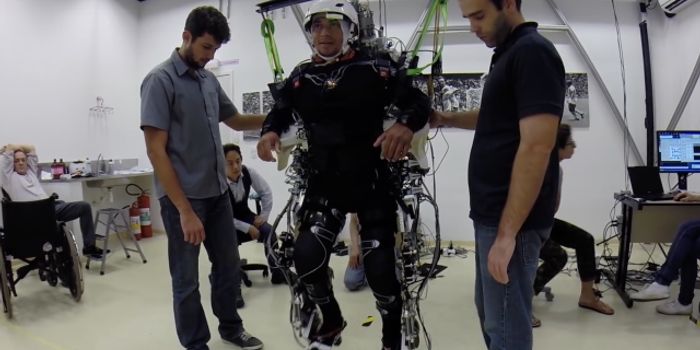

SEP 22, 2016Genetics & GenomicsMost people take for granted that they can walk down the street while thinking about their day. Or drive to work without ...